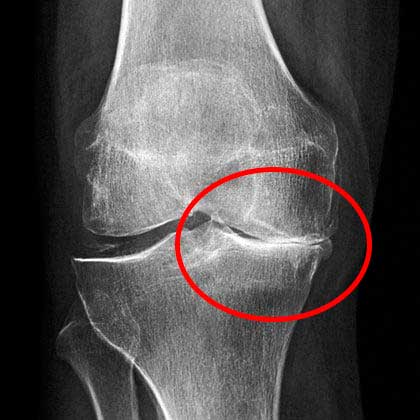

นี่คือภาพรังสีเอกซ์ของข้อเข่าที่ถูกทำลาย

ปัญหาคือ คนส่วนใหญ่มักไม่สนใจอาการแรกเริ่ม พวกเขาคิดว่าอาการปวดเกิดจากความเหนื่อยล้าหรืออายุที่มากขึ้น แต่เมื่ออาการรุนแรงจนทนไม่ไหว โรคก็ลุกลามไปมากแล้ว และการรักษาก็ต้องใช้เวลานานและความพยายามมากขึ้น